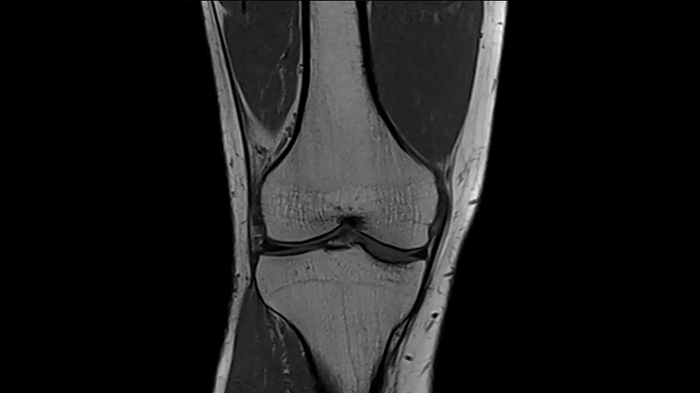

T1 SE

Outstanding T1 imaging of the knee using MAGNETOM Free.Star.

0.3 x 0.3 x 3.0 mm2

TA 2:54 minutes

MAC-ID: 7aaaa0198. Image Credit: Siemens Healthineers